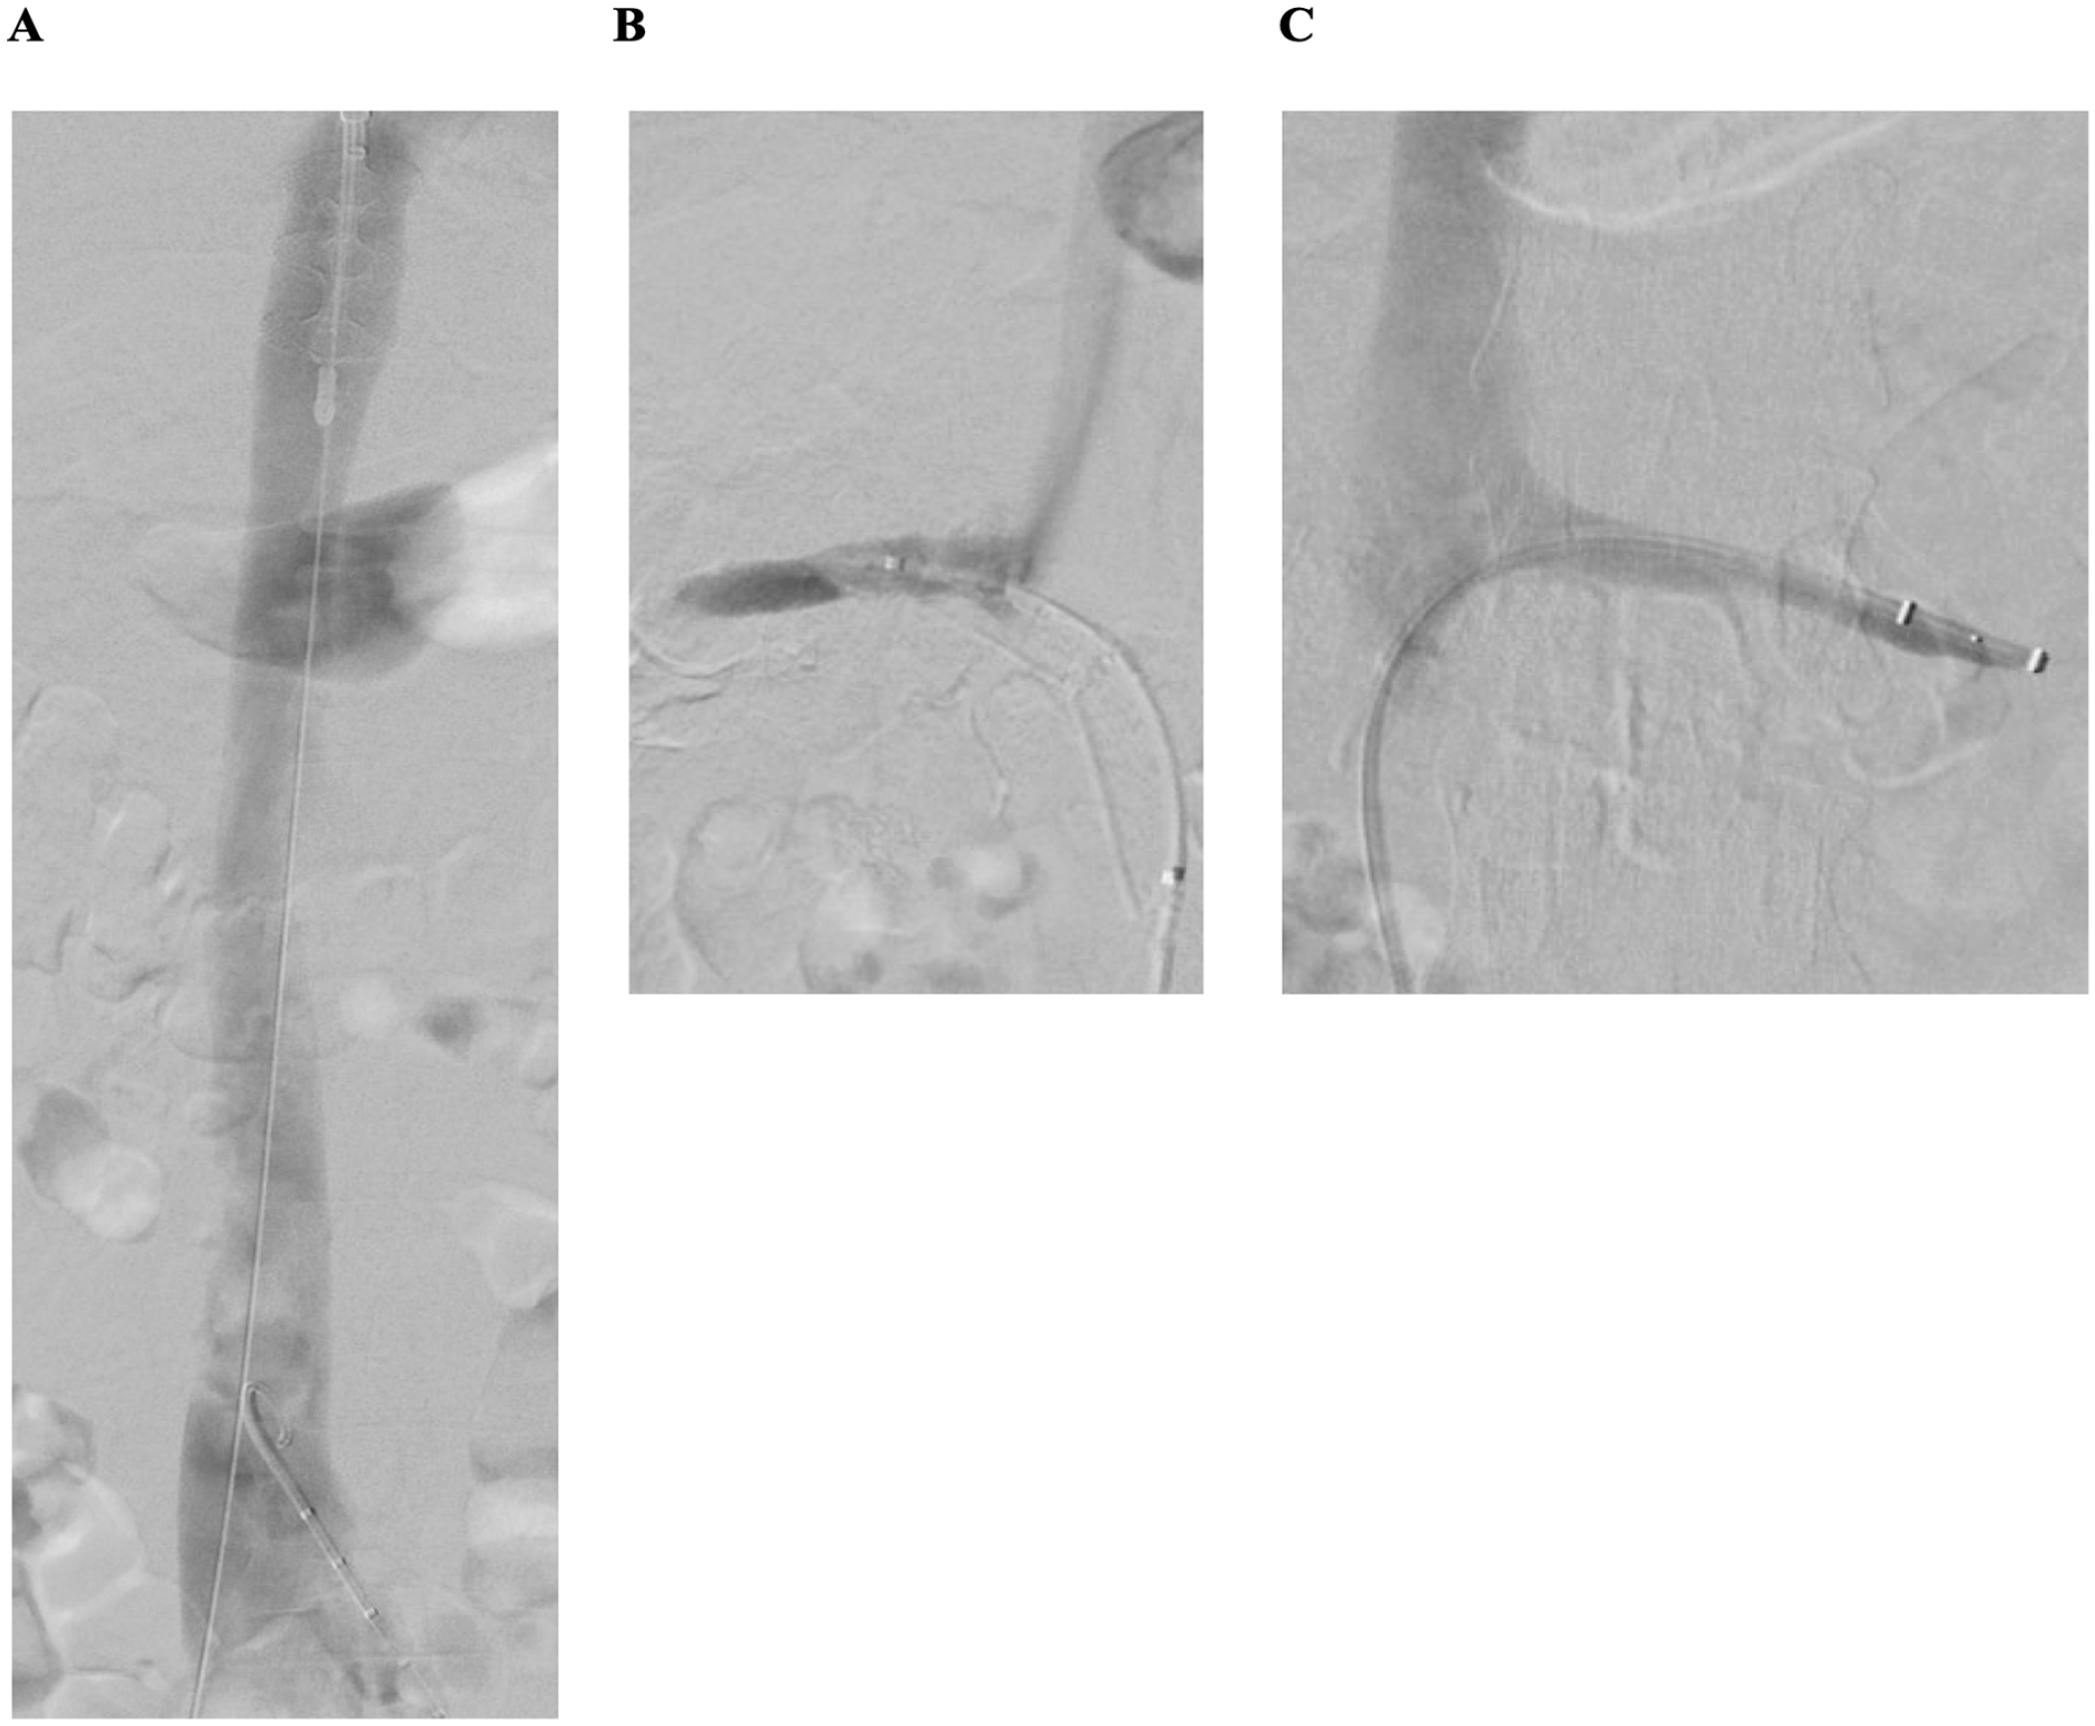

Control phlebography confirmed brisk continuous flow via both iliofemoral venous axes and the inferior vena cava, as well (Figure 2A). Subsequently, thrombectomy of both renal veins was performed using the Angiojet ZelanteDVT catheter (Boston Scientific). To additionally support venous drainage of the kidneys, prolonged balloon angioplasty of both renal veins was performed. Final phlebography showed a spontaneous contrast drainage of both renal veins (Figure 2B and C). Moreover, intravascular ultrasound (IVUS) was used to confirm adequate thrombus removal and to rule out residual venous obstructions. Furthermore, duplex ultrasound confirmed venous flow in both renal veins and in the inferior vena cava. A good flow with outflow into the inferior vena cava was observed in the duplex control, with good respiratory-modulated flow in the inferior vena cava.

Result of catheter-based mechanical thrombectomy of the inferior vena cava, both iliofemoral venous segments, and both renal veins: (A) restored venous flow in the inferior vena cava, (B) restored flow in the right, and (C) and left renal vein after thrombectomy with Angiojet ZelanteDVT catheter (Boston Scientific) of both renal veins.